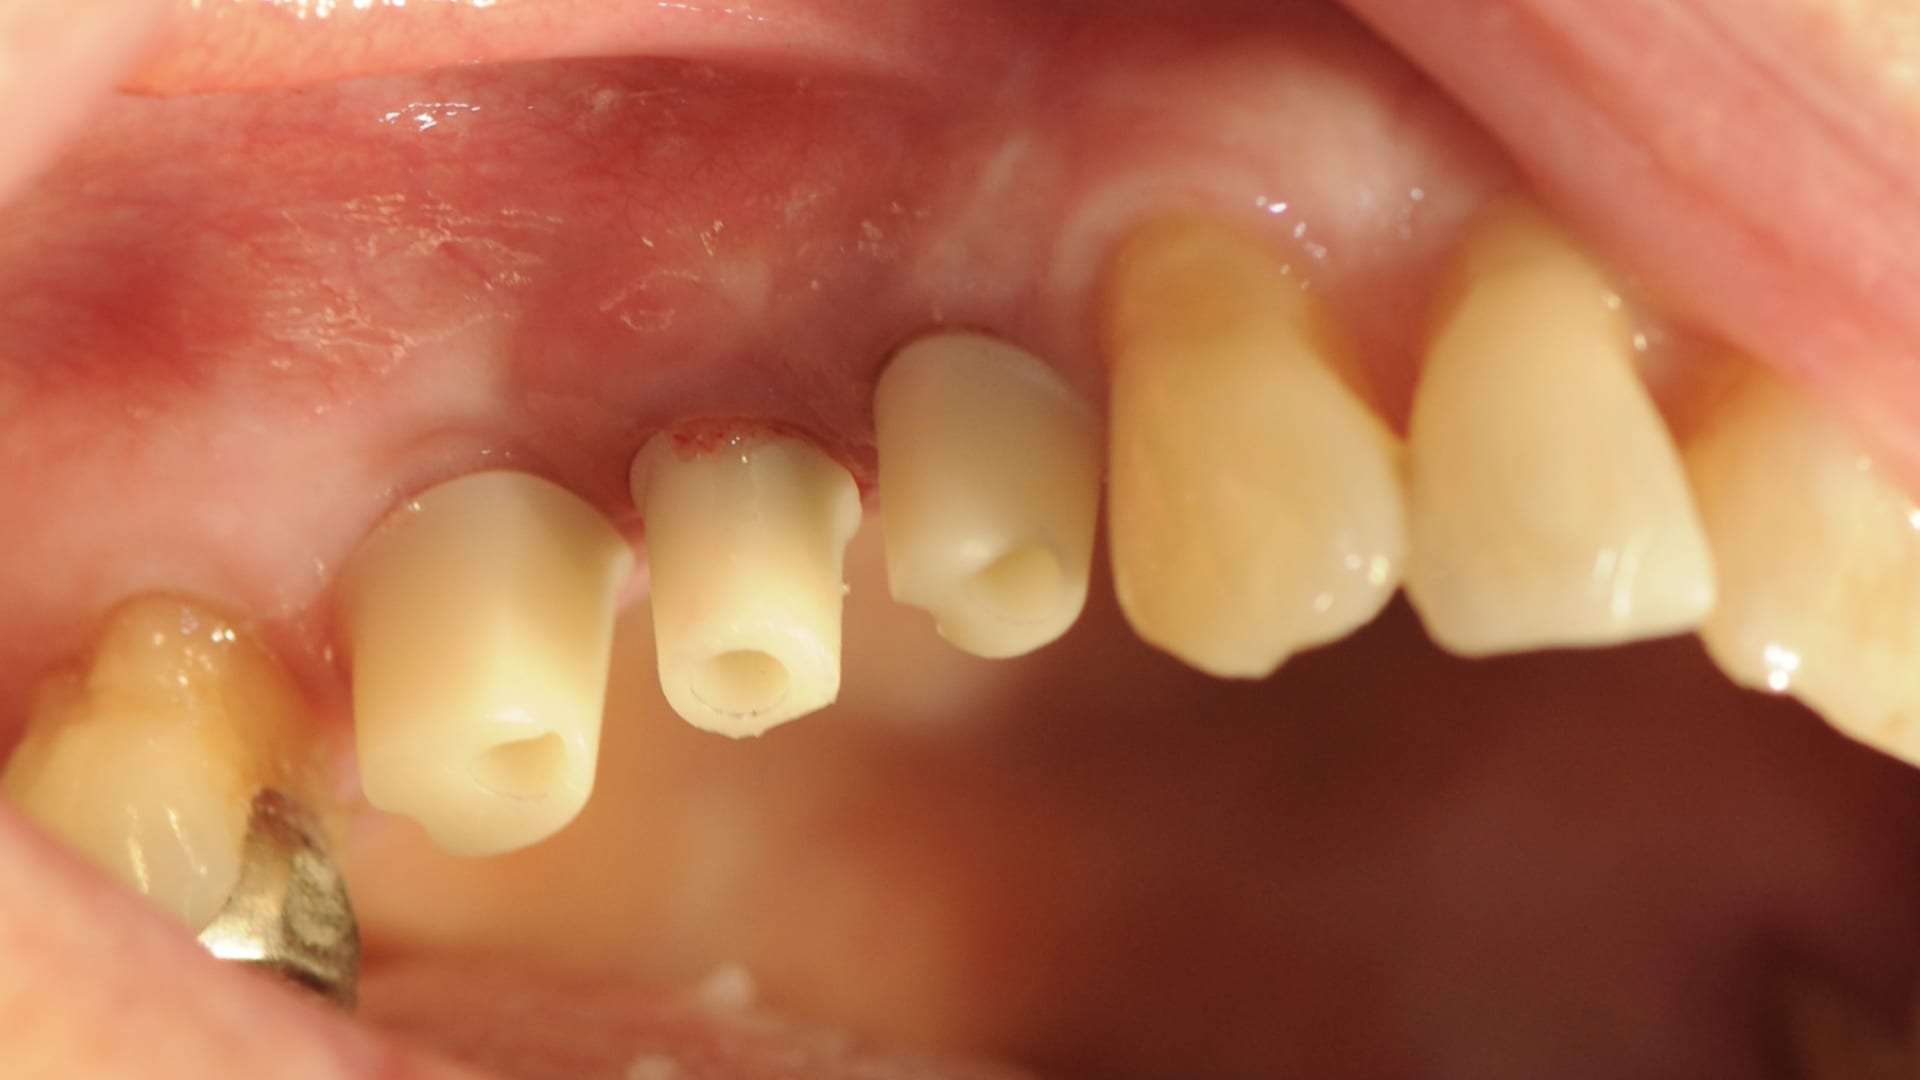

Abb. 1: Ausgangsituation Zahnfilm

Die 76-jährige Patientin stellt sich mit einer seit Jahren bestehenden Brückenversorgung im ersten Quadranten in der Praxis vor (Abb. 1). Die Pfeilerzähne 14 und 16 waren seit Jahren wurzelkanalbehandelt. Der mesiale Brückenpfeilerzahn zeigte eine apikale Beherdung mit Parodontalspaltverbreiterung. Insgesamt wies die Brücke einen Lockerungsgrad von 1 bis 2 auf. Die hauszahnärztlich angebotene erneute zahngetragene Brückenversorgung mit Ausdehnung auf den Eckzahn 13 wurde von der Patientin nicht favorisiert. Deshalb wurde der Patientin eine Entfernung der gesamten Brücke mit Sofortimplantation und Sofortversorgung in Nonokklusion angeraten (Abb. 2). Es wurden in Lokalanästhesie drei Straumann Bone Level Tapered Implantate gesetzt. In derselben Sitzung erfolgte die konventionelle Abformung beider Kiefer. Binnen 24 Stunden wurde ein verschraubtes und verblocktes Langzeitprovisorium aus PMMA auf Klebebasen (Straumann) in Nonokklusion erstellt (Abb. 3). Dieses Langzeitprovisorium verblieb 26 Monate in situ. Nach dem Entfernen des Langzeitprovisoriums zeigten sich perfekt ausgeformte Schleimhautemergenzprofile. Es wurden die entsprechenden Scanbodys eingeschraubt. Die Scandaten wurde mit dem 3Shape Trios 3 von Straumann erhoben und dem Labor übersandt (Abb. 4). Die Farbbestimmung erfolgte über den Scanner.